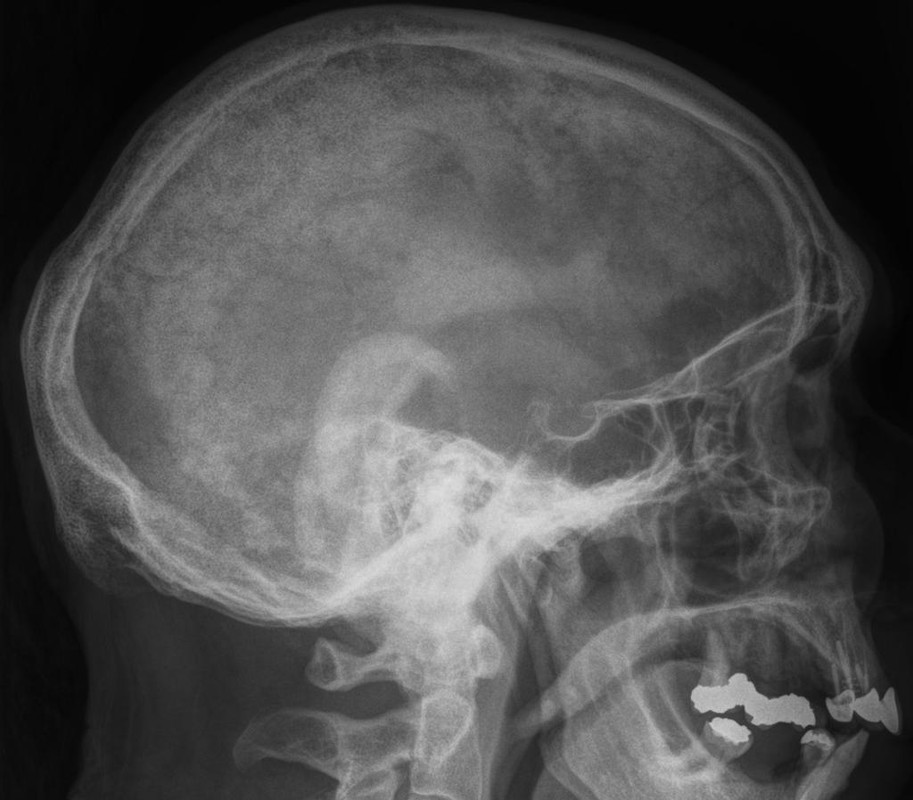

paget disease of bone

A 72-year-old man presents for a routine follow-up in his general practitioner's office regarding his type 2 diabetes and hypertension management. He reports feeling generally well, with no specific complaints of bone pain, fractures, or changes in his hat size. His past medical history includes well-controlled type 2 diabetes mellitus, essential hypertension, and obesity. He denies any recent falls or trauma.During the visit, his vital signs are stable: temperature 36.80C, blood pressure 130/80 mmHg, pulse 70/min, respirations 16/min, and oxygen saturation 98% on room air. Physical examination is unremarkable, with no bony tenderness or deformities noted. Routine laboratory tests ordered during his visit reveal several abnormal findings.Given the patient's presentation and laboratory findings, what is the most likely diagnosis and the initial management strategy?